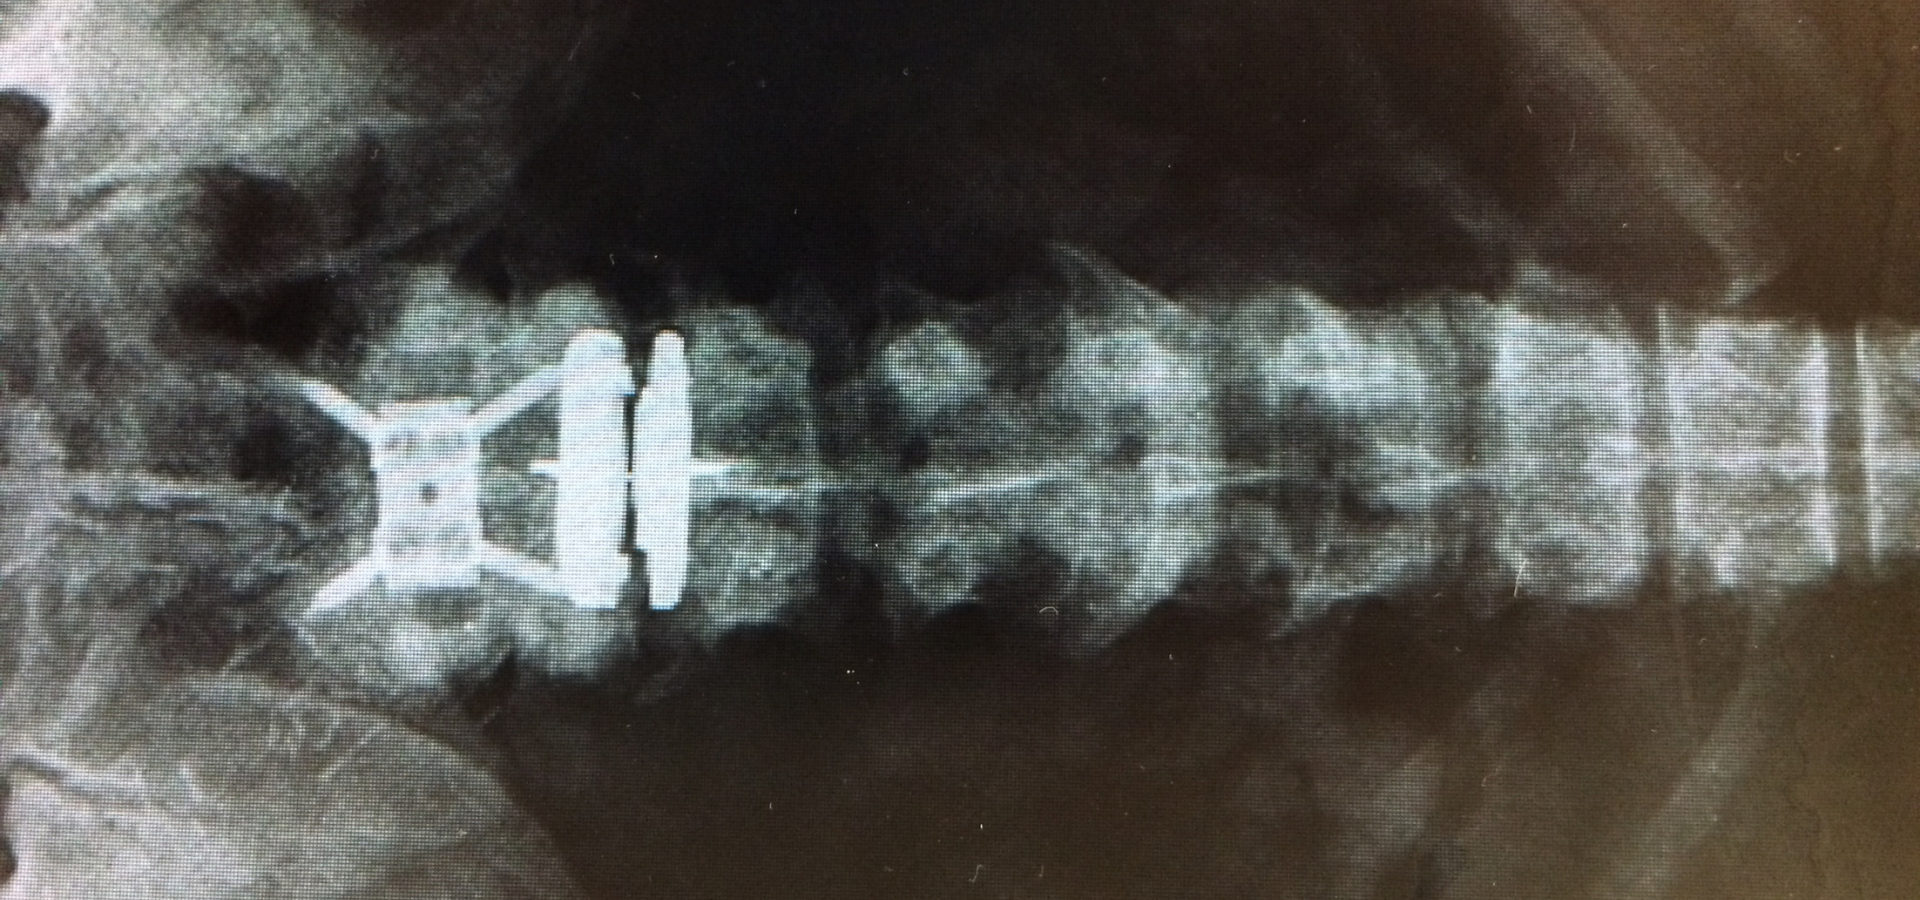

Dr. Geoffrey Liburd stands as a leading force in advancing spinal care in Jamaica and the wider Caribbean. With a commitment to excellence and innovation, Dr. Liburd has dedicated his career to restoring mobility and improving quality of life for…